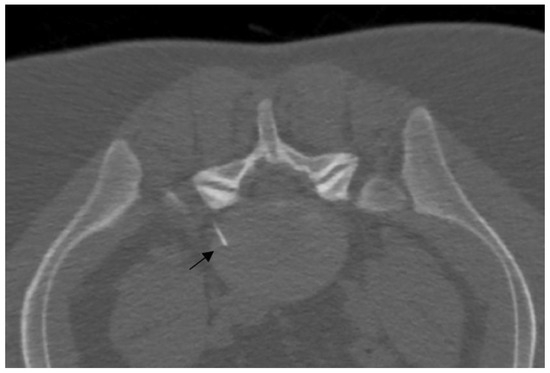

- Napoli, A.; Alfieri, G.; De Maio, A.; Panella, E.; Scipione, R.; Facchini, G.; Albisinni, U.; Spinnato, P.; Nardis, P.G.; Tramutoli, R.; et al. CT-Guided Pulsed Radiofrequency Combined with Steroid Injection for Sciatica from Herniated Disk: A Randomized Trial. Radiology 2023, 307, e221478. [Google Scholar] [CrossRef] [PubMed]